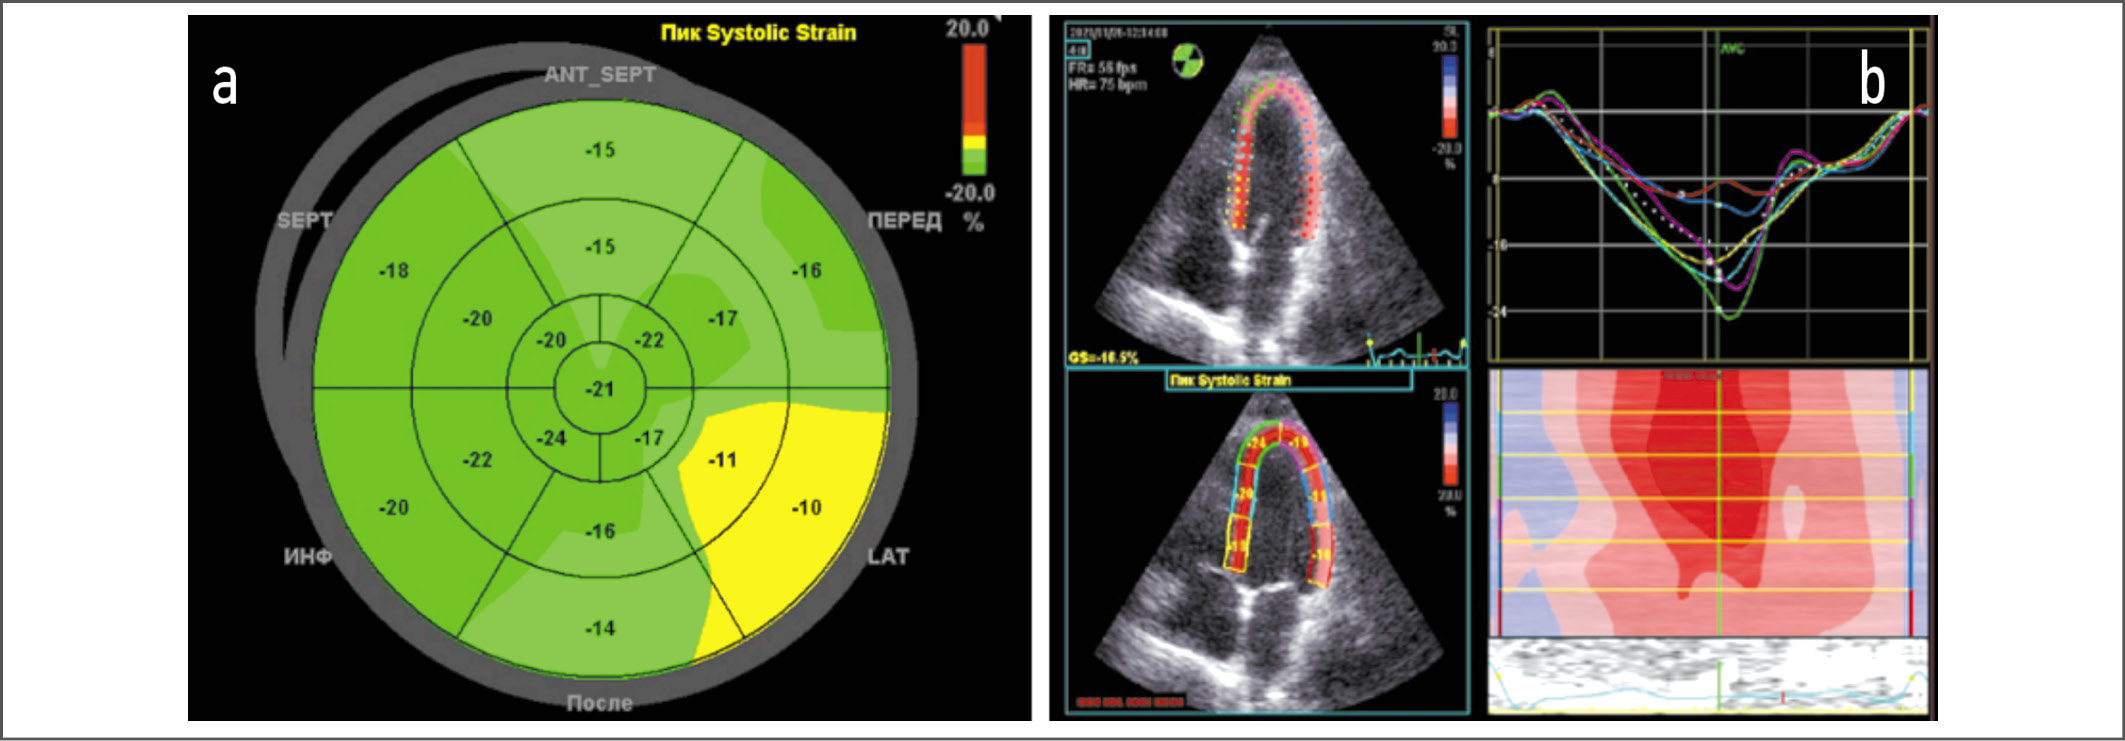

Стандартная электрокардиография: P – 0,11 с, PQ – 0,15 с, QRS – 0,13 с, Q–Tc – 0,47 с. Ритм синусовый, с частотой сердечных сокращений 73 в минуту, полная блокада правой ножки пучка Гиса. По результатам ЭхоКГ установлено, что миокард не утолщен, индекс массы миокарда ЛЖ (ИММЛЖ) составляет 76 г/м², полости сердца не расширены. Индекс объема левого предсердия (ЛП) – 22 мл/м². Фракция выброса ЛЖ по Симпсону – 71%. Ударный объем ЛЖ незначительно снижен (42 мл). Нарушений кинетики миокарда не выявлено. При допплеровской оценке трансмитрального кровотока получено расчетное отношение максимальной скорости раннего наполнения к максимальной скорости позднего наполнения в диастолу (Е/А, ед), составившее 1,4. Пиковая тканевая скорость раннего диастолического смещения (e’) септальной и латеральной частей кольца митрального клапана оказалась равной 6,7 и 8,79 см/с соответственно, усредненные значения показателей e’ и Е/e’ – 7,5 и 17,3 ед соответственно. Отмечена трикуспидальная регургитация 2-й степени, скорость которой составила 3,23 м/с. Створки митрального и аортального клапанов уплотнены. Расчетное давление в легочной артерии – 45 мм рт. ст. Листки перикарда не утолщены, выпота в полости перикарда нет. На рис. 1, 2 представлены результаты допплерографии.

С помощью методики speckle tracking оценена продольная миокардиальная деформация (longitudinal strain). Обнаружено, что глобальный продольный стрейн ЛЖ снижен до 17,5%, при этом наибольшее снижение отмечено в срединном и базальном сегментах переднебоковой стенки ЛЖ (11 и 10% соответственно). Менее выраженное снижение глобального продольного стрейна наблюдали в базальном и срединном сегментах переднесептальной, передней и нижнебоковой стенок ЛЖ (рис. 3).

Рис. 3. УЗ-оценка продольной систолической деформации миокарда: a – топографическое представление данных продольного анализа деформации в сегментах миокарда ЛЖ (bull's eye – мишень). Отчетливо видно значительное снижение продольной деформации в срединном и базальном сегментах переднебоковой стенки ЛЖ (11 и 10% соответственно); b – график временной зависимости продольной деформации всех перегородочных и боковых сегментов. Наблюдается снижение пиковой продольной деформации в нижнем и срединном боковых сегментах.

Fig. 3. Ultrasound assessment of longitudinal systolic deformation of the myocardium: a – topographical presentation of data from longitudinal analysis of deformation in segments of the LV myocardium (bull's eye - target); b – longitudinal strain time plot of all septal and lateral segments.

РКМП характеризуется нормальными или сниженными диастолическими и систолическими объемами одного или обоих желудочков, нормальной толщиной их стенок. Исторически считается, что систолическая функция желудочков сердца при РКМП не страдает, однако признаки латентных нарушений сократительной способности миокарда можно обнаружить у большинства пациентов. Тканевая допплерография митрального кольца может зафиксировать снижение систолических волн (s-волн), притупление формы ранних и поздних диастолических волн в зависимости от степени вовлечения в патологический процесс предсердий [16]. Оценка деформации ЛЖ по методике speckle tracking способствует выявлению скрытых нарушений систолической функции при нормальной фракции выброса ЛЖ у пациентов с патологией миокарда различного генеза [17]. РКМП характеризуется преимущественным инициальным снижением глобальной продольной деформации (что может быть связано с ухудшением функции субэндокардиальных волокон на фоне инфильтративных и фиброзных изменений), а в последующем – радиальной и циркулярной [18, 19]. В нашем наблюдении констатированы признаки латентной систолической дисфункции преимущественно в срединном и базальном сегментах переднебоковой стенки ЛЖ. Контрастная МРТ позволила обнаружить очаги фиброза в МЖП и стенках предсердий. Эти фиброзные изменения топически не совпали с полученными при анализе продольного стрейна зонами. Сочетание методов кардиовизуализации в данном случае позволило более детально оценить области лучевого повреждения миокарда, степень их выраженности и характер.